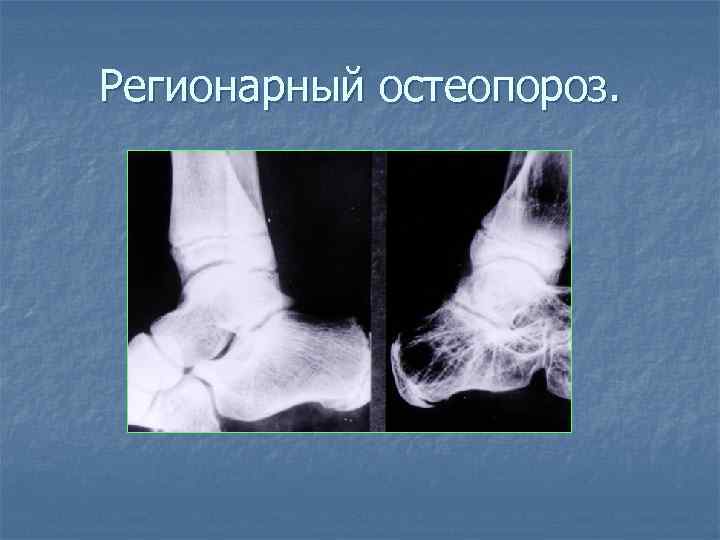

Регионарный остеопороз.